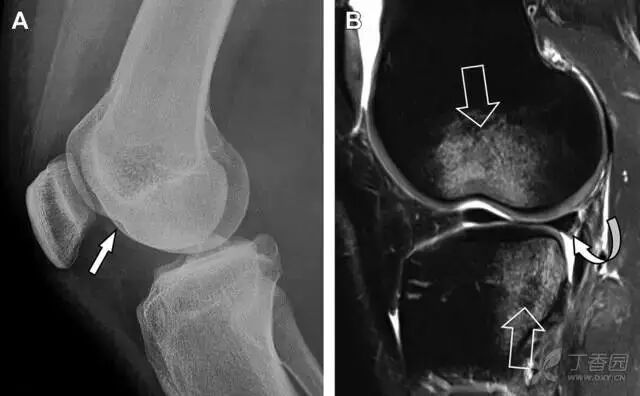

股骨外侧髁凹陷征(图 2)

图 2 扭伤后的股骨外侧髁凹陷征。A 侧位片示股骨外侧髁凹陷。B MRI 矢状位 T2 加权像示股骨外侧髁及胫骨后外侧骨挫伤(空箭头)。胫骨近端随着后交叉韧带撕裂发生移位,露出外侧半月板的后角(弧形箭头)